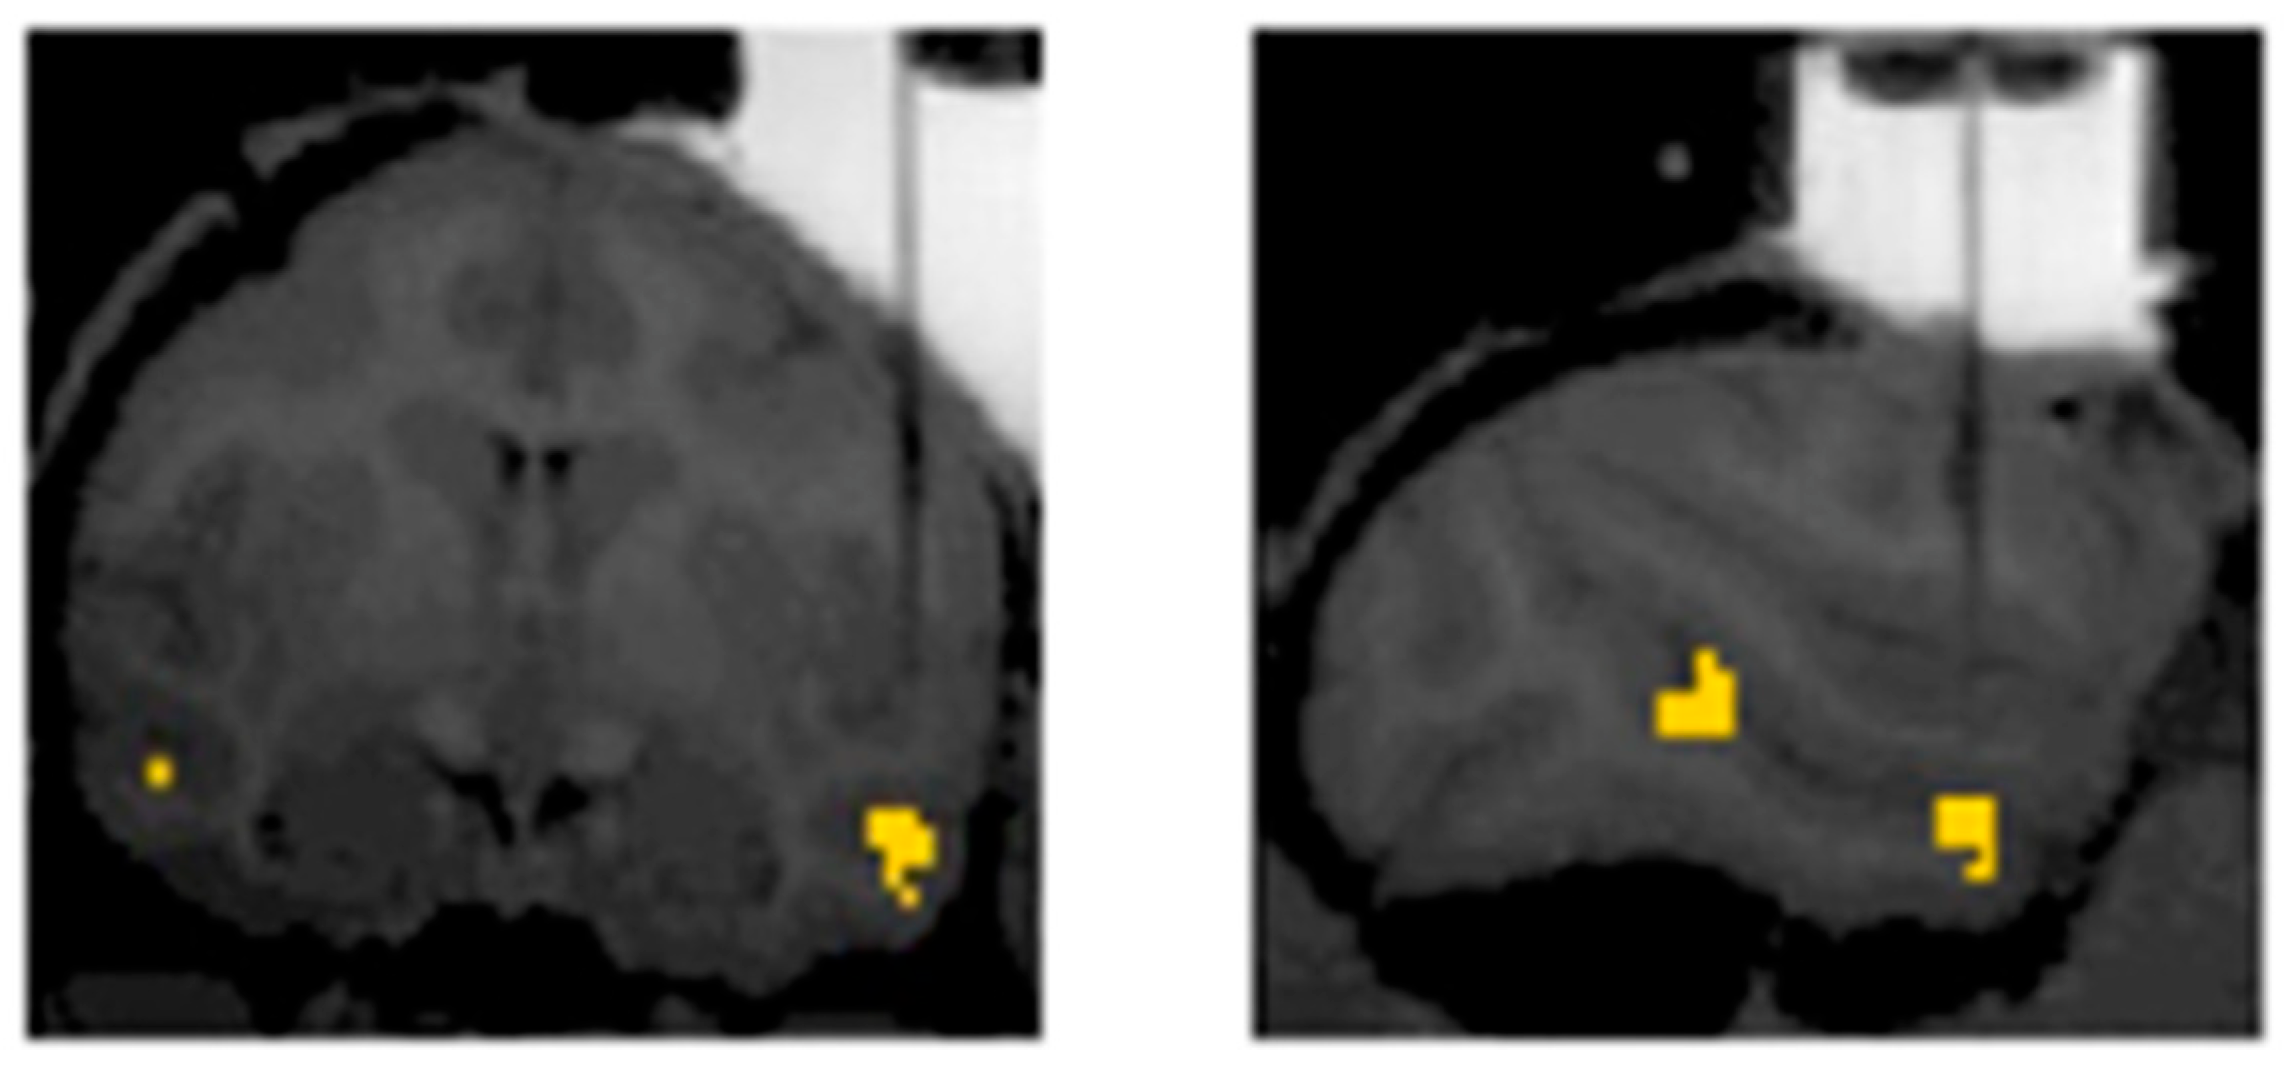

3. The Present